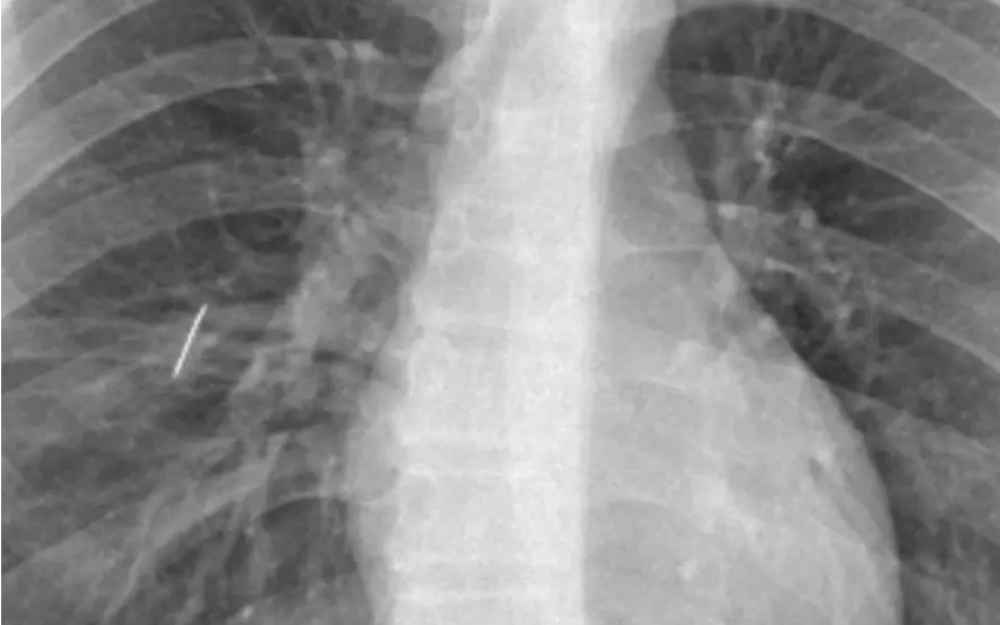

El servicio de Cirugía General del Hospital Interzonal San Juan Bautista realizó una intervención quirúrgica compleja e inédita para extraer una aguja de coser alojada en el pulmón de un paciente de 16 años, oriundo de Tinogasta, quien ingresó por guardia tras sufrir un accidente doméstico. El hecho ocurrió cuando el joven se apoyó sobre una caja que contenía un objeto metálico, que le provocó un trauma penetrante de tórax.

Tras una primera atención en su lugar de origen, fue derivado al hospital, donde se confirmó la presencia del cuerpo extraño en el pulmón. El equipo de Emergencias, ni bien ingresado, realizó el drenaje torácico mediante la colocación de un tubo para la evacuación de aire, secreciones y sangre; como el pulmón no lograba expandirse debido a la presencia del objeto, se procedió a la planificación de la resolución quirúrgica.

En este sentido, el Dr. Lestussi explicó: “Se trató de un trauma penetrante de tórax con un objeto metálico que resultó ser una aguja de coser, clavada en el pulmón. Era un caso que no podía derivarse por el riesgo que implicaba el traslado, por lo que la resolución debía hacerse en nuestro hospital, y con mucha satisfacción podemos decir que lo realizamos profesionales del hospital”.